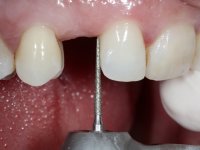

To define the dental zone to be covered by the Maryland bridge retainers, the patient was asked to perform maximum intercuspidation movements, and the contact points were marked with articular paper. Tooth preparation of the interproximal surfaces was made, to create a prosthetic insertion axis. It was sought that the mesio-distal diameter at the incisal level was equal to the diameter mesio-distal at the cervical level, that is to say, the interproximal walls were parallelized. Tooth preparation was done with fine grain diamond drills, and later polishing was done with abrasive discs. Color information was collected even before confection of the impression, to avoid dehydration of the arcade. Definitive impression was made using wash technique impression with silicone of heavy and regular consistency, both with fast setting, and a working plaster model was prepared in the lab. A laboratory scanner was used to scan the working model, and later, the infrastructure for the Maryland bridge was made using a CAD-CAM process. Ceramic was placed on this subframe. A ceramic adhesive was applied to the internal surface of the wings and connectors, which would enable bonding to the adjacent teeth. The adhesive bridge was bonded in the mouth following the conventional bonding technique. After bonding, the protrusion and laterality movements were carefully checked to avoid undesirable contacts.